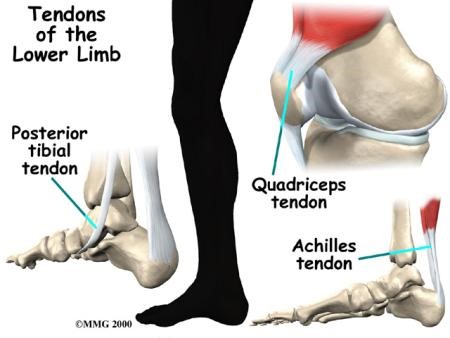

Doctors use different terms to describe specific types of tendon problems. When tendonitis arises, it is typically observed in the joints—particularly those in the lower limb.

Posterior Tibial Tendonitis

Posterior tibial tendonitis, which is also called tendon dysfunction, is a common problem that affects the ankle and foot. It develops due to inflammation of the posterior tibial tendon. If the tendon tears, it loses the ability to properly stabilize the arch of the foot and can lead to painful flatfoot. This issue is usually caused by age-related degeneration.

Patellar and Quadriceps Tendonitis

Patellar and quadriceps tendons are located near the knees. Patellar tendonitis refers to inflammation of the tendon that connects the patella (kneecap) to the shinbone. Quadriceps tendonitis occurs when inflammation develops in the quadriceps tendon, which is located directly above the patella where it connects the thigh muscles to the top of the patella. Problems in the knee tendons mostly occur in active individuals who regularly engage in running or jumping. Patellar tendonitis is also called jumper's knee.